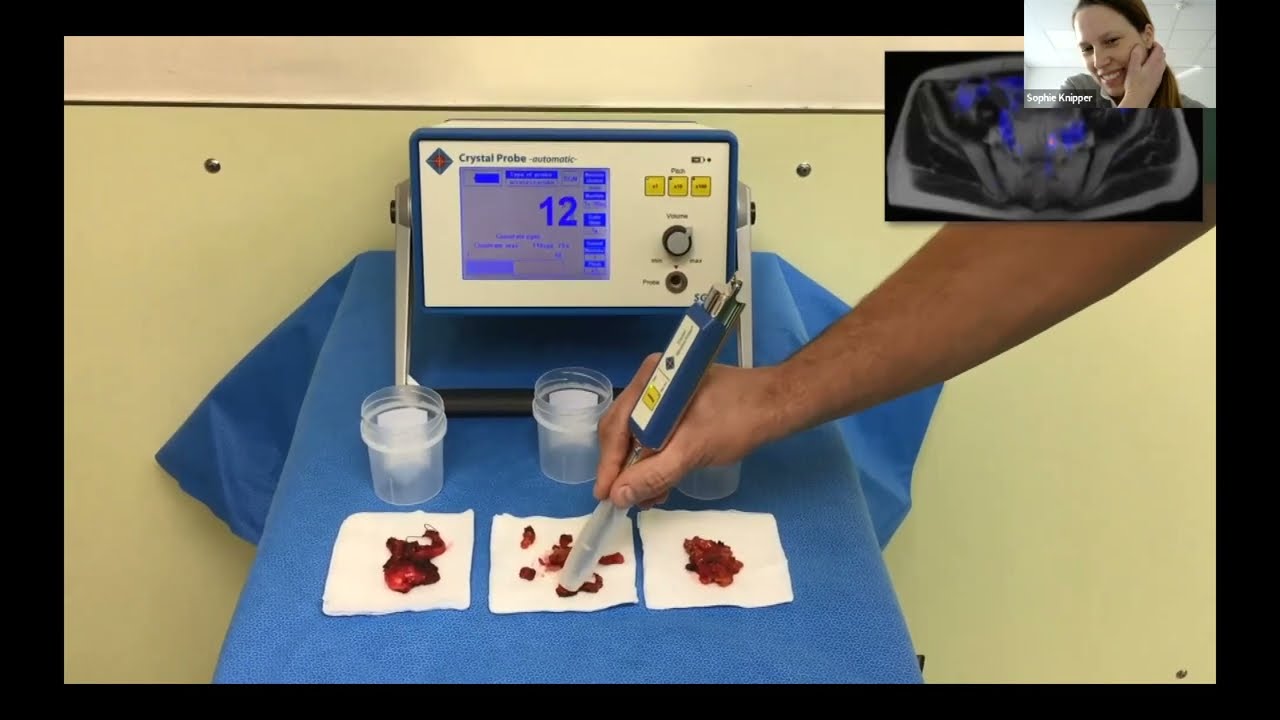

Session 3: Recent Advances in Intraoperative Detection of Nodal Metastases in Prostate Cancer

Masterclass, Robotics, Surgeon, Urology, Video Library ';